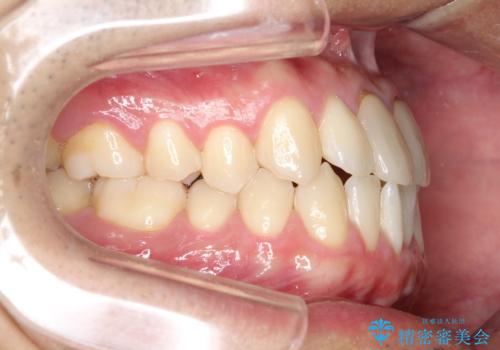

上下のがたつきをインビザラインで目立たない矯正

- 前歯のガタガタを主訴に来院されました。

上下の前歯のガタガタと左上の歯が反対にかんでいる状態でした。

上下の歯と歯の間をわずかに削り並べる計画としました。

目立たずに歯並びがよくなり、前歯に装着されたセラミックも壊さずに矯正治療が終了し満足していただけました。